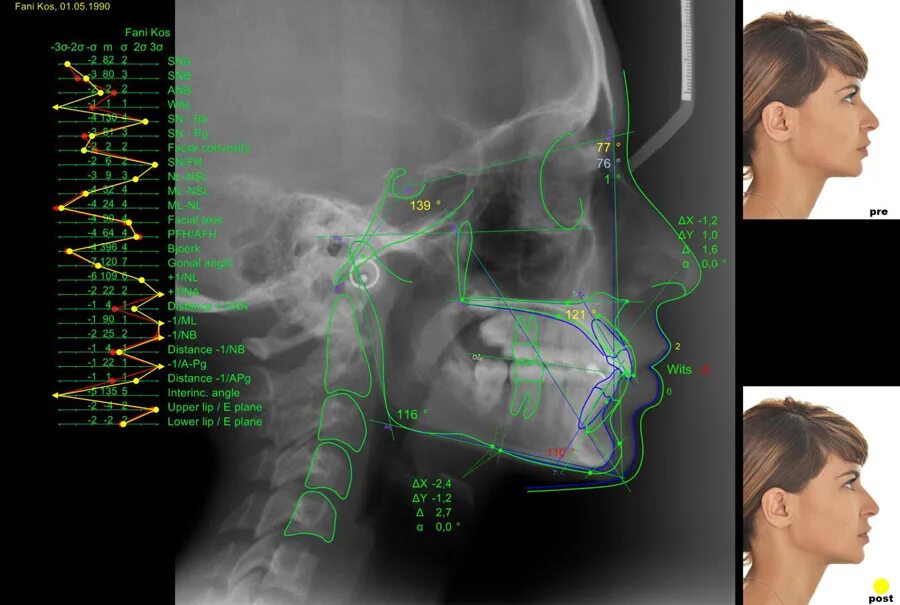

Трг проекции